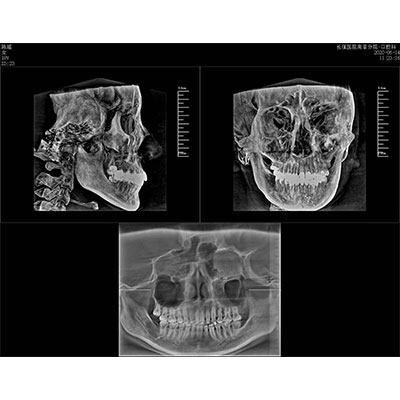

该款牙科CBCT产品采用动态平板探测器,获得三维图像的同时还具有数字化全景功能,广泛应用于口腔颌面外科、正畸科、正颌外科、种植科、牙体科、颞下颌关节科等术前术后。

三维重建任意断层

专有三维重建算法,可提供任意位置高清断层影像。

多平面组合重建

可同时观察轴向面、冠状面和矢状面图像,方便临床诊断。

Clinical picture

临床图片